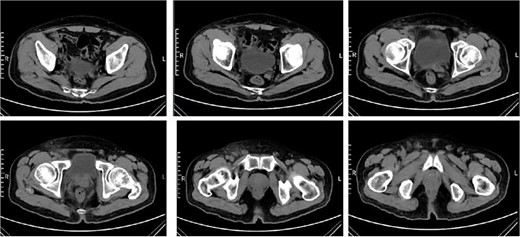

Empiric treatment with IV ampicillin and blood culture was initiated due to suspected lymph node inflammation. On Day 15, the patient’s symptoms worsened, with increased lymph node size to 2 × 4 cm, oral ulcers, and abdominal lesions. Labs showed leukocytosis with neutrophilia (white blood cells 10.74 × 109/L, neutrophil percentage 85.4%,) and elevated CRP (123.2 mg/L). Computed tomography (CT) scans revealed: (i) Local fibrous cord in the lower lobes of both lungs. (ii) Multiple small nodules in both lungs. (iii) Splenic enlargement. (iv) Possible inflammatory changes in the right pelvic and inguinal regions with multiple enlarged lymph nodes (Fig. 4).

CT scans revealed inflammatory changes and enlarged lymph nodes in the right pelvic and inguinal regions, leading to a diagnosis of fever due to inguinal lymphadenitis. The antibiotic treatment was intensified to include IV cefoperazone sodium, sulbactam sodium, and metronidazole.On postoperative Day 16, the patient had persistent fever (37.3°C–38.7°C) and symptoms, with normal rheumatoid factor and immune panel but elevated erythrocyte sedimentation rate (ESR) (53 mm/H), IL-6 (164.95 pg/ml), and CRP (153.2 mg/L),and white blood cells, procalcitonin (PCT) were normal. Despite IV sulbactam sodium and metronidazole, fever persisted on day 20 (37.3°C–39.2°C), with worsening symptoms. Blood cultures were negative. On the 22nd postoperative day, the pathological report indicated destruction of the lymph node structure with visible coagulative necrotic foci and focal necrosis of histiocytes, which was consistent with necrotizing lymphadenitis. The patient was started on oral prednisone acetate (15 mg three times a day). After 5 days of treatment, the patient’s body temperature gradually returned to normal, the pain in the right inguinal lymph node subsided, its size decreased to 2 × 2 cm, the oral ulcers began to heal, and the abdominal papules and pustules resolved (Fig. 5).